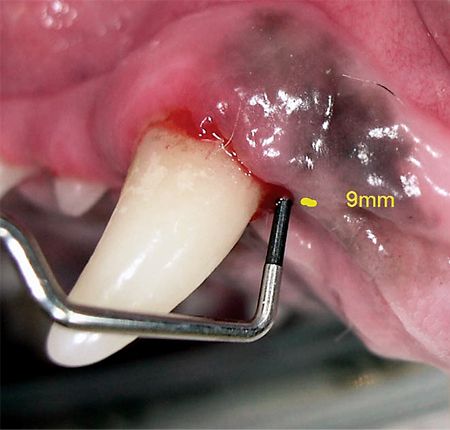

Stage 3 periodontal disease is diagnosed when 25 to 50 percent support loss has occurred. Unless the client and patient are committed to stringent daily plaque prevention, often the best choice is tooth extraction. Patients generally do better without teeth when compared to living with painful dentition.

When there are significant probing pocket depths present, an apical position flap can be used to decrease the pocket (Photos 7 & 8). If areas of gingival recession are creating support loss without pocket depths, teeth cleaning plus stringent home care are options. In cases in which bone defects have resulted as a consequence of periodontal disease, bone grafting can be used to preserve or restore the alveolar height. This technique is effective in treating deep, narrow, three-walled infrabony pockets, such as palatal defects, that do not extend into the nasal cavity.

Photo 7: A 9-mm periodontal pocket.